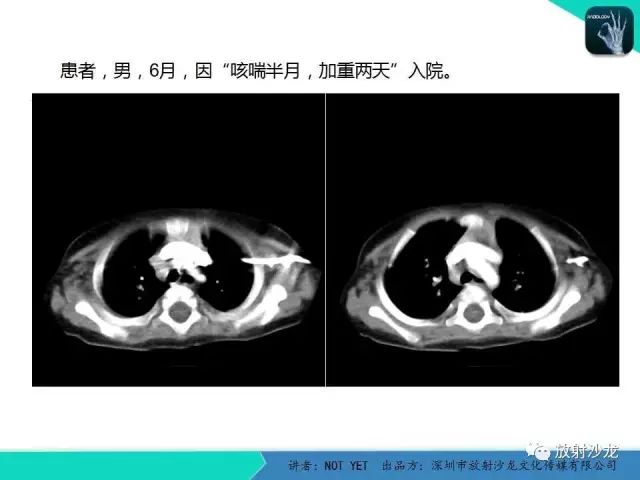

动脉导管未闭1例CT影像表现

【病例】动脉导管未闭1例CT影像表现